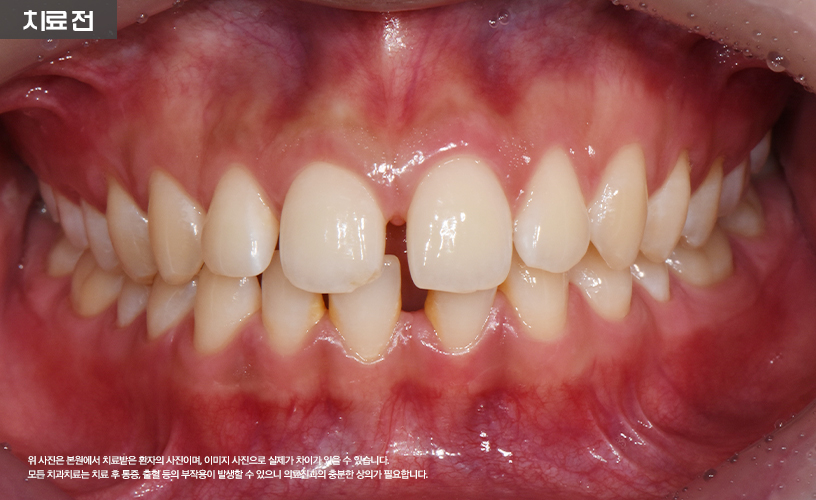

"투명교정 치료 사례"

상기 환자분은 상, 하악 앞니 벌어짐으로 인해

교정 치료를 고민하시다가 본 원에 내원하셨습니다.

본 원에서는 정밀한 검진을 통해 환자분의

앞니 벌어짐 상태를 점검한 다음

기존 일반적인 교정 치료 방식이 아닌

시스루 얼라이너 투명교정 치료가 수립되었습니다.

투명장치를 착용하여 치료가 진행되어

환자분의 일상생활에도 큰 지장을 주지 않으면서도

교정치료가 진행되기 때문에 환자분 역시

매우 만족해하셨습니다.